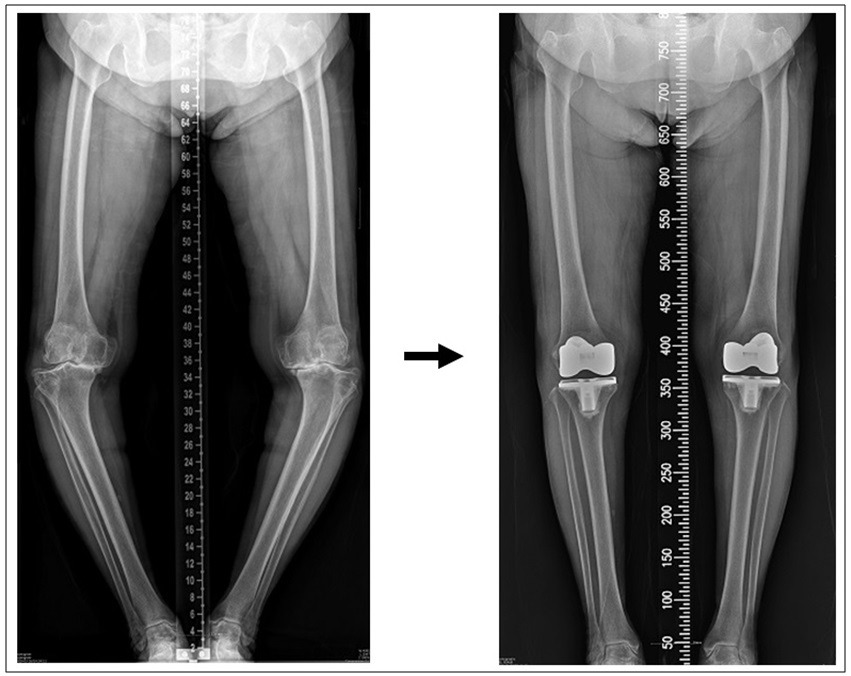

무릎 주위 뼈를 잘라 O자형 다리(오다리 변형)를 11자 다리에 가깝게 하지의 정렬을 교정해 주는 ‘근위경골절골술’도 많이 시행하고 있습니다. 이 수술은 무릎의 내반 변형이 관절염의 원인이라는 것이 확실하고, 관절염 중기 정도일 때 적합한 수술이라, 통증이 심한 말기 관절염에는 효과를 보기 어렵습니다. 뼈를 잘라 변형을 교정하고 금속판을 이용하여 다시 뼈를 붙이는 수술이라서 뼈가 어느 정도 붙을 때까지 수술 후 4-6주간 보조기 착용과 목발 보행을 해야 하고, 수술 중 골절이나 수술 후 불유합 등 여러 가지 합병증이 발생할 수도 있으니 전문가와 세밀한 상담이 꼭 필요합니다 (아래사진) [27].

S Battaglia. HTO surgery. In Surgical techniques in TKA and alternative procedures 2015

비교적 최신 수술방법인 ‘부분치환술’은 손상된 관절의 일부분만 정밀하게 다듬어낸 후 사이즈가 매우 작은 인공관절로 대체하는 획기적인 수술 방법으로 무릎 관절 인대들은 손대지 않으므로 정상적인 무릎 기능이 유지되어 걸음걸이가 자연스럽고, 양반자세를 하고 앉거나 쪼그려 앉는 데 별 무리가 없게 됩니다. 따라서 무릎을 많이 구부리는 생활습관을 가진 동양인, 특히 우리나라 사람들에게 아주 적합한 수술 방법입니다. 수술 부위도 5-6cm으로 작고, 무릎 조직의 일부분만 제거하기에, 수술 다음날 보조기도 없이 혼자 걸을 수 있을 정도로 회복이 빠른 것이 부분치환술의 장점입니다. 하지만 매우 정밀한 수술이라 경험이 적은 의사가 수술할 땐 여러가지 합병증이 생길 수 있다는 점을 염두에 두셔야 합니다 [30].

'부분치환술' 술 중 사진 & 술 후 X-ray

* 부분치환술 후 양반다리, 쪼그려 앉기, 꿇어 앉기가 가능해진 실제 환자 사진.